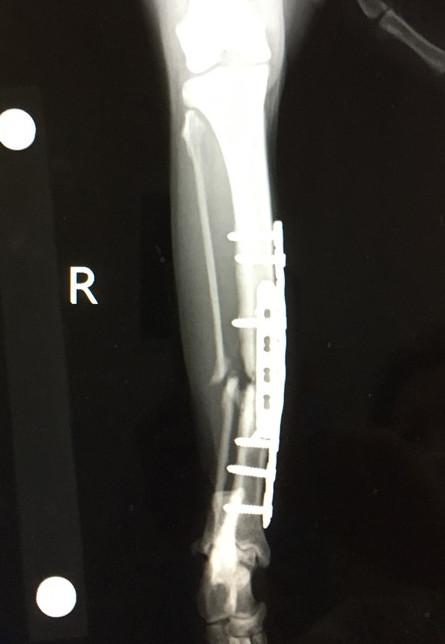

9月5日 手術から約1ヶ月(6週間)後

9月6日 手術から約1ヶ月(6週間)後

札幌病院、経過観察 プレート少し曲がる